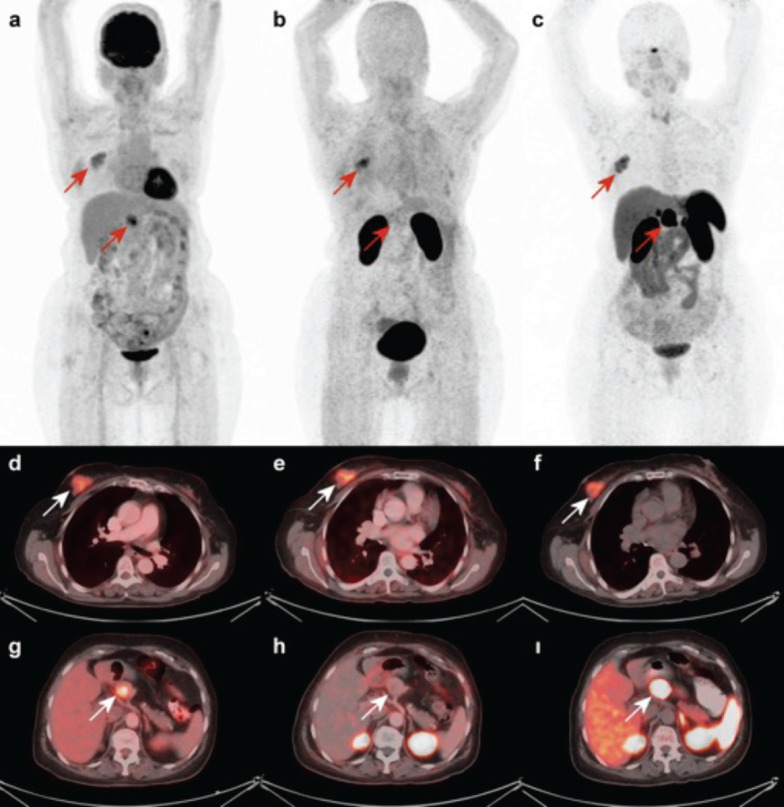

Cancer Integrin Imaging with [68Ga]Ga-Trivehexin PET/CT for a Patient with Breast Cancer and Neuroendocrine Neoplasm: A Case of Both (18F)FDG PET/CT and [68Ga]Ga-DOTATATE Positive but Integrin αvβ6 Negative Lesion on [68Ga]Ga-Trivehexin PET.

Integrins play crucial roles in the migration of tumor cells during angiogenesis and metastasis. Consequently, αvβ6-integrin-targeted positron emission tomography (PET) radiopharmaceuticals have been developed and tested in humans, with clinical trials highlighting their applications in idiopathic pulmonary fibrosis and carcinomas. However, data on integrins are limited, and the role of [68Ga]Ga-Trivehexin tomography/computed tomography (CT) PET/CT is not well-established. Some studies have suggested that [68Ga]Ga-Trivehexin PET/CT is more specific than 18F-fluorodeoxyglucose (18F-FDG) PET/CT, which can yield false-positive results. It has been shown to be more efficient in evaluating pancreatic lesions and head and neck tumors. The role of [68Ga]Ga Trivehexin PET/CT in neuroendocrine tumors is not yet clearly defined. In our case, integrin was negative in the pancreatic neuroendocrine tumor but positive in the breast lobular tumor. Additionally, we observed that the lobular carcinoma lesion in the right breast is somatostatin receptor+positive on [68Ga]Ga-DOTATATE PET/CT.